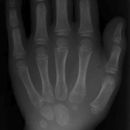

Hand schräg: Zitherspieler (chirurgisch, 2. Ebene)

Indikation

Fraktur

Lagerung

sitzend - seitlich zum Tisch

1. Möglichkeit - d.-v.

Hand seitlich mit Kleinfingerseite aufstellen und nach vorne fallen lassen, sodass die restlichen Finger und der Daumen den Bildempfänger mit den Fingerkuppen berühren (Fächerhaltung)

2. Möglichkeit - v.-d. bei Fraktur MC 4-5

Hand seitlich mit Kleinfingerseite aufstellen und ca. 20° nach hinten fallen lassen

Daumen abduziert & Finger gestreckt

Zentralstrahl

Senkrecht auf Objektmitte

Einblendung

proximal einschließlich Proc. styloideus radii und ulnae

Anmerkung

Trotz Schräghaltung werden die Finger weitgehend seitlich projiziert.

Fragestellungsabhängige Einblendung mögl. z. B. Mittelhand

Qualitätskriterien

Darstellung der ganzen Hand mit schräger, überlagerungsfreier Darstellung der Mittelhand und des Handgelenkes, Metacarpale 4 und 5 überlagern sich leicht in der Basis bei der 1. Möglichkeit.